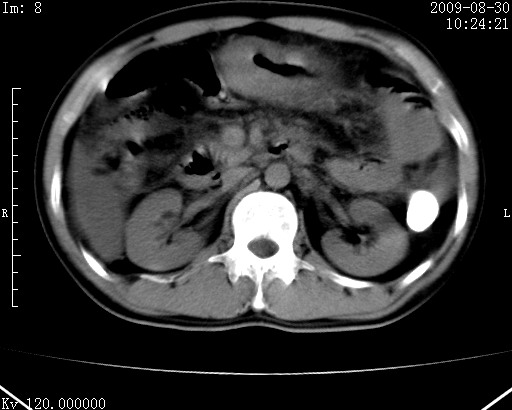

患者唐某,男31岁,已婚,本地务农。

自述入院前两天一次进食较多冷饮之后,出现阵发性上腹部疼痛,次日加剧伴恶心、呕吐,呕吐后症状稍减轻。食欲差。大便每天1-2次,量少,暗红色水样。小便赤。无畏寒、发热、咳嗽等呼吸道症状。无高血压及胃病史。

检查:体温、血压及脉搏正常.皮肤无黄染,浅表无淋巴结肿大。左腹肌紧张,左上腹有压痛,无反跳痛,可触及包块。

生化:钾、钠、氯、钙、ph正常,总胆红素和直接胆红素稍高,空腹血糖稍高。

尿淀粉酶:1256 u/l(正常60-401)。

血常规:wbc 22.4x109/l gr88% ly9.6%其余基本正常。

胃镜:急性胃炎。立位腹平片:未见异常。

下面是ct平扫,降结肠内是对比剂。

术前影像诊断:上段空肠急性缺血性坏死并腹水。建议手术治疗。

术中见上段空肠约70cm长范围坏死,从屈氏韧带远端约10cm处开始。坏死肠管肿胀变形变色,管壁明显环形增厚,部分聚成大肿块,无扭转和套叠。肠系膜上动脉分支内广泛泥沙状血栓。肠切除。

临床诊断:肠系膜上动脉梗塞并急性肠坏死。

开始时我们科也有人认为是套叠,最后统一意见,不考虑肠套。我们看到的“靶征”,“晕圈征”,“双圈征”实际上只是单根肠管的横断面。坏死肿胀后肠壁各层的密度不一样。

左侧腹小肠腔管壁明显增厚,部分内示靶征,走行异常,部分肠系膜绳样改变,肝包膜下及肠间较多液体密度,然梗阻近端肠腔积气不明显。

考虑;肠扭曲伴肠坏死。